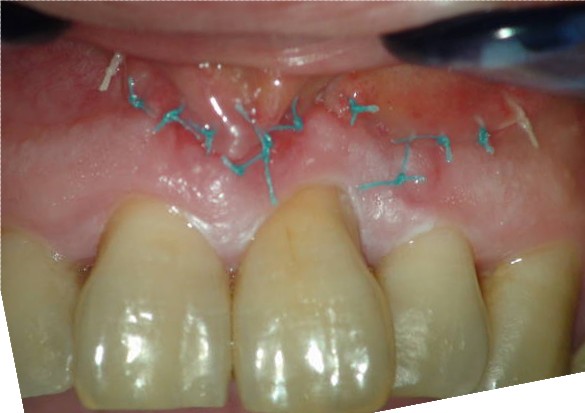

Una vez todo estudiado, preparamos el caso:

Pasados 4-5 días pasaríamos a retirar la sutura.